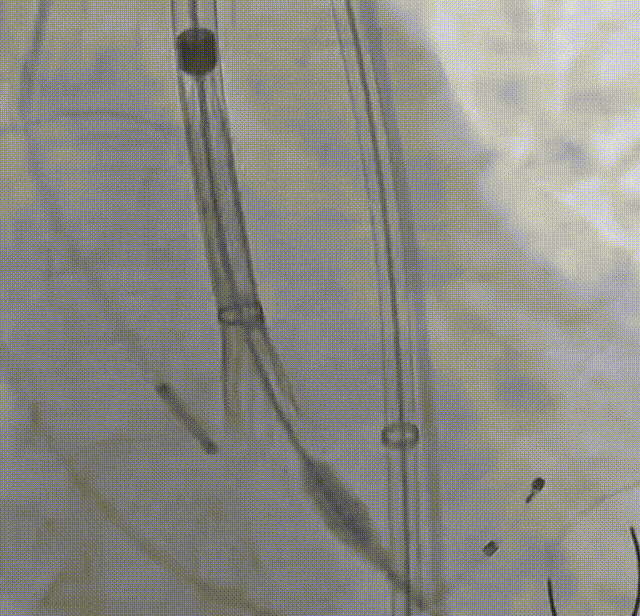

罗建方教授 广东省人民医院(点击查看专家详细简历) 设计本为临床需,耐久守护好芳华:任何医疗产品的设计初衷与最终归宿,都应落在 “临床获益” 这一核心上。尤其在 TAVR 领域,年轻患者预期寿命长,术后瓣膜的长期性能直接关乎其生活质量与生存预后。瓣膜耐久性问题,是落到临床实践中亟待突破的关键课题。传统瓣膜在长期使用中,可能因结构老化、功能退化等问题,难以满足年轻群体数十年的健康需求,二次手术风险也随之攀升。因此,产品设计必须直面这一临床痛点:通过材料革新增强抗钙化性能及生物相容性,以技术突破延长瓣膜有效使用寿命。此次临床应用的预装干瓣Prostyle A®是TAVR领域的革新理念,干瓣预期会为临床提供更耐久性的保障,实现了与临床需求的精准对接,为年轻群体的瓣膜治疗提供更坚实的保障。 李捷教授 广东省人民医院(点击查看专家详细简历) 干瓣技术求革新,性能兼顾护临床:干瓣的技术革新在创新的同时需要和临床实际需求深度耦合,兼顾TAVR术中的核心考量点。临床操作中,瓣膜能否顺利过弓,直接影响手术效率与安全性。Prostyle A®短瓣架设计及第二台阶的柔顺设计,术中操作丝滑;同时,瓣膜植入后的径向支撑力必须平衡得当,才能实现稳定锚定;释放后造影显示:瓣膜形态舒展,轻度瓣周漏,舒张压升高,冠脉开口未受影响;瓣周漏是影响术后效果的关键隐患,双层裙边设计通过多重密封机制降低反流风险,为患者长期获益筑牢防线。这些性能的协同优化,最终目的是让干瓣在临床中真正做到 “好用、耐用、安全用”,为患者预后提升提供坚实支撑。 患者病史 患者因 “活动后气促伴头晕 2 月” 入院。 现病史:2月前无诱因出现活动后气促,休息后缓解,伴头晕,夜间阵发性呼吸困难。超声检查发现:主动脉瓣重度狭窄并重度返流(跨瓣流速 4.3m/s,峰值压差 73mmHg);主动脉 + 冠状动脉 CTA 提示主动脉瓣显著钙化,升主动脉及分支粥样硬化,冠状动脉轻度狭窄(RCA 狭窄 30-40%)。 既往史:高血压病史 15 年,规律服药,血压控制稳定。 术前诊断:非风湿性主动脉瓣狭窄伴关闭不全(重度)、心功能 II 级(NYHA)、高血压病 2 级(高危)、冠状动脉粥样硬化。 术前CT 三叶瓣,瓣叶增厚中度钙化,右无交界钙化粘连,瓣环径25.1mm,LVOT 25.1mm,直筒型结构;窦部空间足够,升主未见增宽,瓣环水平夹角55°;冠脉开口位置佳,无冠脉风险;入路散在钙化、外周双侧入路无明显迂曲,双侧内径可、中分叉,左右侧均能够支持20F 大鞘通过。 造影角度及入路 手术策略 右侧股动脉为主入路,左侧为辅助入路;使用20球囊预扩,准备AV26瓣膜,冲洗口朝向3点钟方向送入输送系统性能,初始定位真实瓣环0位释放,最终锚定约瓣下3mm,工作位评估瓣膜稳定性与冠脉情况。 手术过程 根部造影 20mm 球囊预扩无明显腰征 术中使用26号瓣膜,瓣膜释放贴边迅速 80% 工作位观察瓣膜位置良好 释放后造影显示:瓣膜形态舒展,轻度瓣周漏,舒张压由术前30mmHg升为 60mmHg,冠脉开口未受影响。 术后超声:跨瓣流速降至1.6m/s,平均压差降至5 mmHg,心功能显著改善。 Prostyle A®预装干瓣——助力临床最优化解决方案: 1. 抗钙化与耐久性:Micro-EX™专利技术提升瓣膜抗钙化能力,适配患者瓣叶中度钙化的解剖特点,为长期疗效提供保障。 2. 柔顺过弓与精准定位:短瓣架设计 + 远端超滑涂层,确保患者输送系统过弓顺畅;瓣架流入端微直筒设计,让定位贴边更迅速,减少了手术时间; 3. 80% 可回收设计:便于术中调整观察,减少起搏时间,从而减少并发症。 4. 简化手术流程:预装设计缩短操作时间,20F 大鞘兼容外周入路,降低血管损伤风险。 · END ·